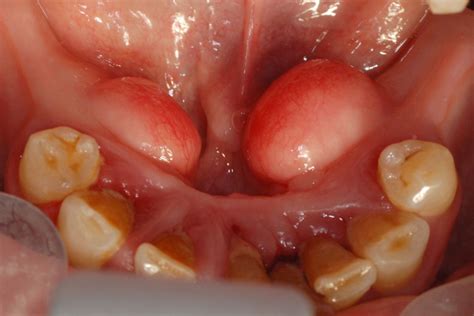

Torus mandibularis refers to a bony outgrowth, or exostosis, that develops along the lingual aspect (the side near the tongue) of the mandible, or lower jawbone. These growths are essentially dense, cortical bone covered by a thin layer of mucosal tissue. When browsing Torus Mandibularis images, you will typically observe that they appear as rounded, hard, and sometimes lobulated projections located above the mylohyoid line, usually in the area of the premolars.

These growths are generally asymptomatic, meaning they do not cause pain or discomfort in the vast majority of cases. They develop very slowly over many years and are often discovered incidentally during a routine dental cleaning or exam. While they can be single, they frequently occur symmetrically on both the left and right sides of the jaw.

Identifying these growths involves understanding their physical properties. Because they are composed of healthy, dense bone, they feel rock-hard to the touch and are immobile, as they are part of the jawbone itself. Here are the primary characteristics often depicted in Torus Mandibularis images:

• Location: Typically found on the lingual (tongue) side of the lower jaw, most commonly near the premolar teeth.

• Consistency: Extremely hard to the touch; they do not feel soft, spongy, or fluid-filled.

• Surface Texture: Can be smooth, nodular, or irregular in shape.

• Symmetry: Very often, they appear bilaterally, meaning they are present on both the left and right sides of the jaw.

While you may find many Torus Mandibularis images online that look remarkably similar to what you see in your own mirror, you should never attempt a self-diagnosis. What appears to be a torus could potentially be an abscess, an oral cyst, or another type of growth that requires a different treatment path. A dental professional uses a combination of clinical inspection and, if necessary, dental radiographs (X-rays) to confirm the diagnosis. Because tori are made of dense bone, they show up clearly as opaque, white masses on X-rays, allowing your dentist to distinguish them definitively from soft-tissue lesions.